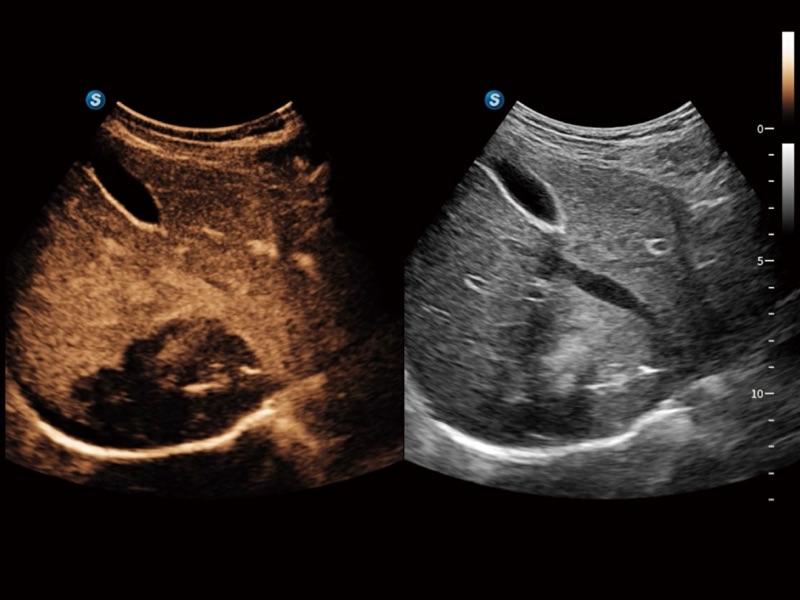

便携式彩色多普勒超声诊断系统

作为开立医疗全新打造的高端全域笔记本超声,X11集成了当前先进的硬件架构和精密的设计工艺,提升多科室临床医生在常规影像检查中的诊断能力,为临床提供全面的诊疗支持。

信噪比提升

分辨率&均一性提升